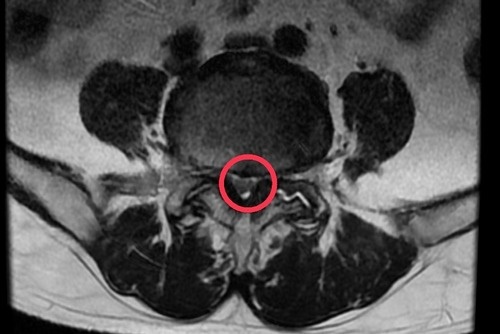

左圖、右圖:磁振造影顯示黃先生腰椎滑脫,神經受到壓迫。